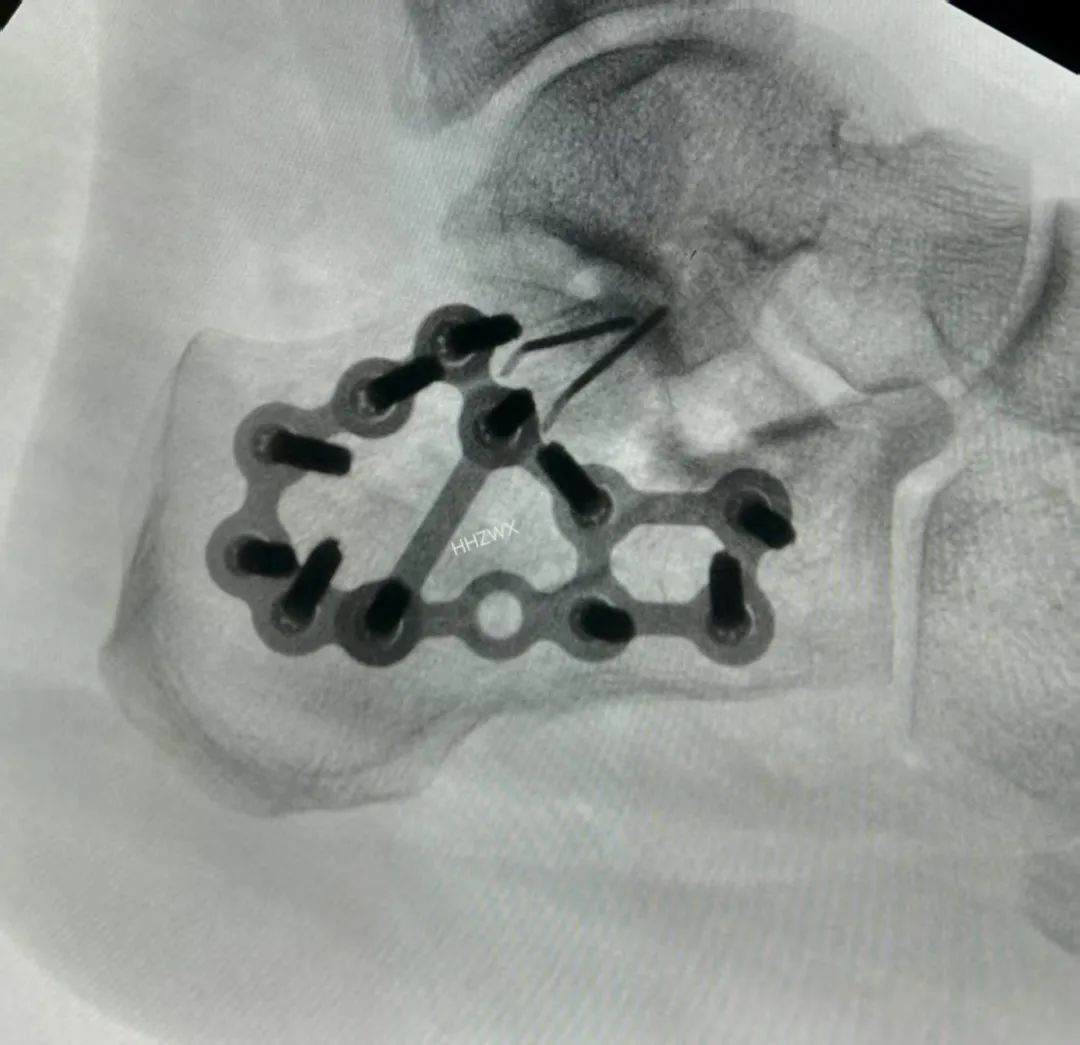

理想情况下,外侧钢板需要跨越跟骨结节骨块和前突骨块,同时螺钉通过钢板固定内侧载距突骨块。(这个也是复位的最佳标准了)

大L型切口,克氏针牵拉撬拨复位内翻畸形,D图的临时克氏针固定内翻畸形这个技巧很重要,最后复位关节面。F、G图显示术后透视可见解剖复位。

解决内翻之后,复位关节面,同时复位G角和舌型骨折块,辅助克氏针临时固定,可以很好的固定骨折。术中可以看到解剖复位。

这一例也是采用同样的方法,复位内翻之后,克氏针临时固定,钛针固定载距突方向复位关节面。最终解剖复位。